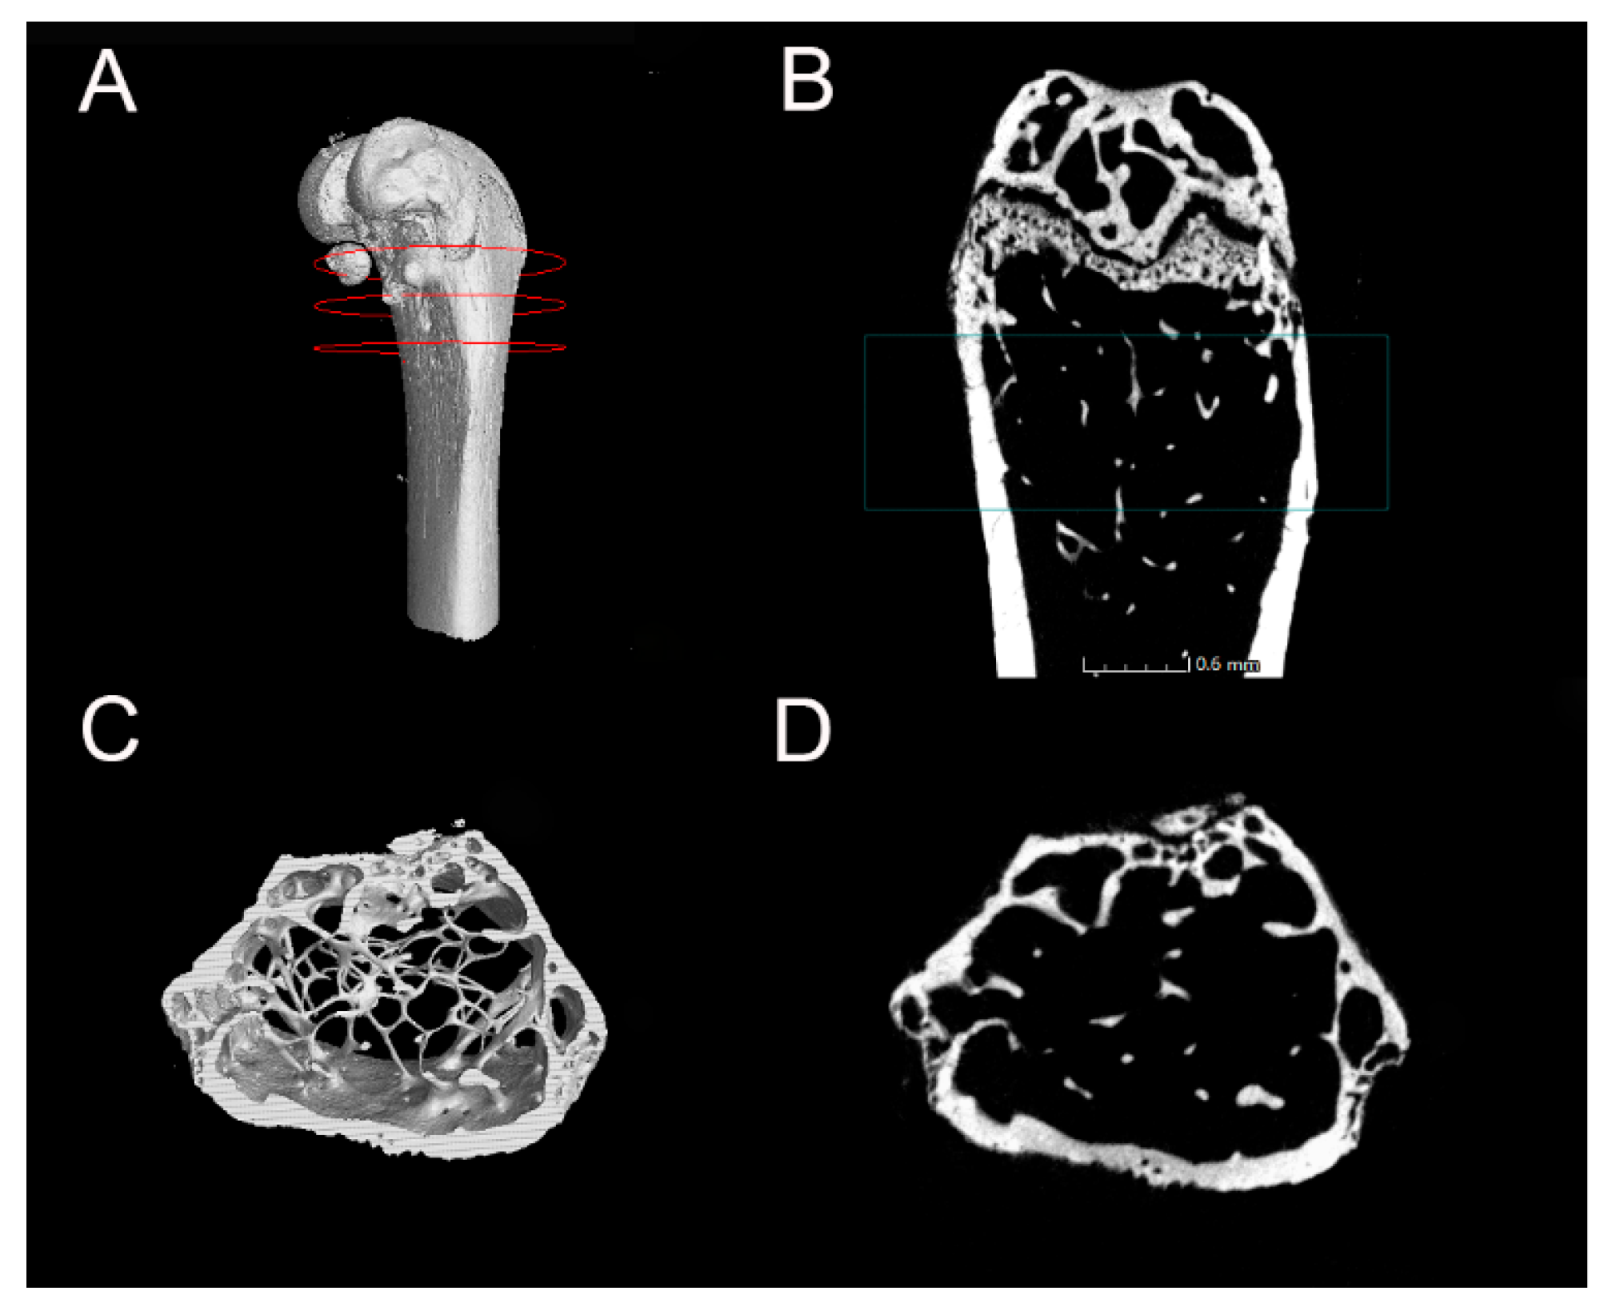

2.4. Microstructure of the Distal Femur

4.7. Micro-CT Analysis